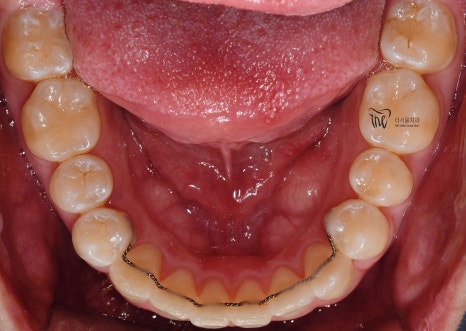

구강 내 사진을 보면, 전형적인 Open bite 의

형태를 띄고 있는 것을 보실 수 있습니다.

그 정도는, 그렇게 심하지는 않으나

치아교정 을 받지 않는다면 턱관절 에

더 큰 문제를 일으킨다는 것을 본인 스스로도

잘 알고 있었기 때문에 저에게 진료를

의뢰했었습니다.